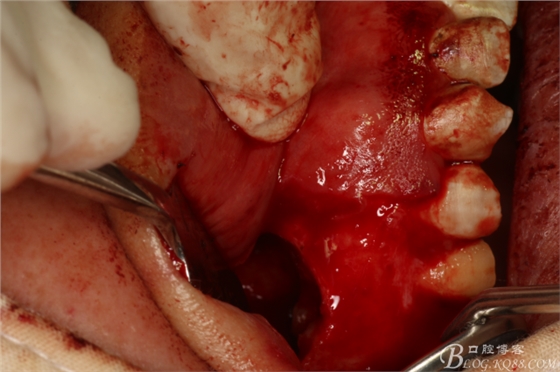

圖7.做角形切口

圖8.翻瓣

圖9.暴露出16根尖上方的囊壁